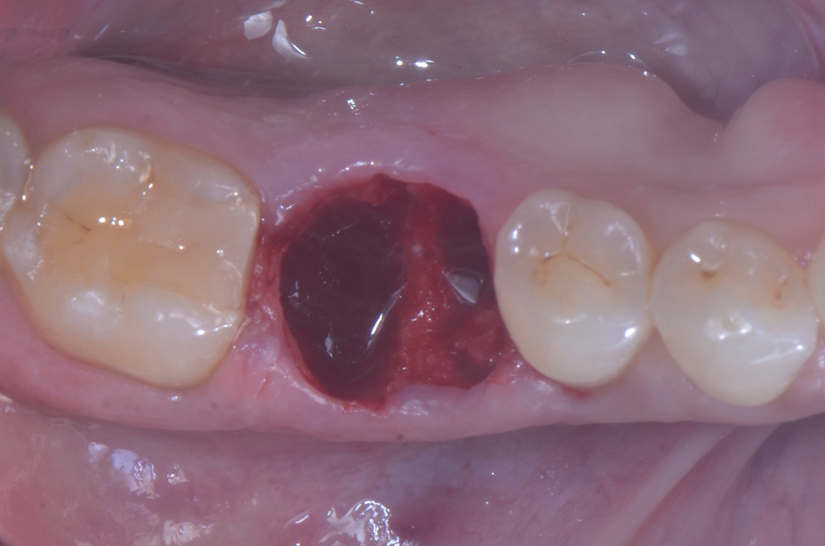

O paciente apresentou fratura vertical mésio-distal no elemento 46. Foi planejada a exodontia minimamente traumática e instalação imediata do implante Maestro Superiore (Implacil Osstem) utilizando uma guia prototipada. Após a exodontia, o implante foi instalado seguindo o protocolo de cirurgia guiada. O GAP vestibular foi preenchido com o Extra Graft. Um cicatrizador personalizado impresso com haletas facilitadoras foi capturado com resina flow e instalado. Após 30 dias, foi realizado escaneamento indireto para obtenção do perfil de emergência, utilizando protocolo digital com sobreposição do cicatrizador escaneado para confecção da coroa definitiva em zircônia policristalina estabilizada por ítria.

O uso de cicatrizadores personalizados, especialmente confeccionados por impressão 3D, tem ganhado destaque por permitir a conformação tecidual progressiva, facilitando a reprodução do perfil de emergência no fluxo digital6,7. A captura do cicatrizador com haletas de retenção com resina flow e seu posterior escaneamento são etapas críticas para assegurar a fidelidade da transferência do perfil de emergência e garantir um planejamento restaurador mais previsível8.